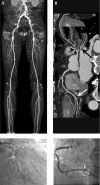

Patients and methods: We retrospectively enrolled 103 PAD patients without cardiac symptoms or known CAD. All patients underwent cardiac computed tomography (CT) and lower extremity CT within 1 month and were categorized as nonsignificant CAD, single-CAD, or multivessel-CAD. The coronary calcium scores (CCS) were quantitatively measured according to the Agatston method and LECS were semi-quantitatively measured according to the presence of lower extremity calcification in the segment. The extent of CAD was evaluated according to the presence of ≥ 50% luminal diameter stenosis in the segment of CAD.

Results: LECS in multivessel-CAD were significantly higher than those in nonsignificant CAD (10.0 ± 5.8 versus 4.0 ± 3.1, P < 0.001). LECS significantly correlated with CCS (r = 0.831, P < 0.001) and the extent of CAD (r = 0.631, P < 0.001). Multivariate regression analysis demonstrated LECS and log-transformed CCS were independent predictors for multivessel-CAD. In receiver operating characteristic curve analysis, the diagnostic performance of LECS was 0.807 (95% confidence interval = 0.724-0.891, P < 0.001) for predicting multivessel-CAD.